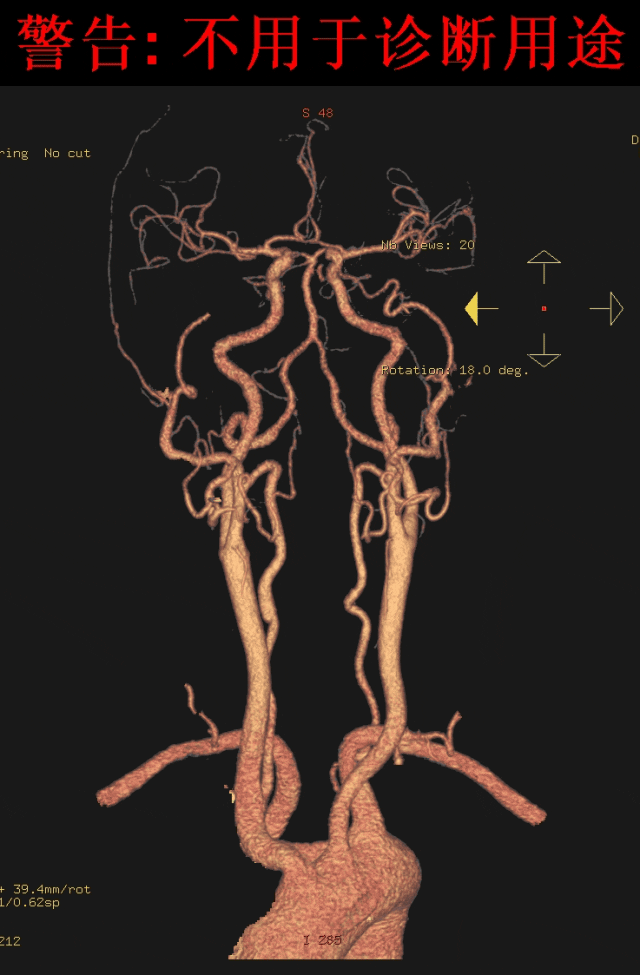

CT 血管造影见迷走右锁骨下动脉起始于主动脉弓或降主动脉;

MIP 冠状位显示主动脉弓下缘“象鼻样”发出的血管,常由左下向右越过中线向上延伸,轴位则常为“鸟嘴样”改变。

手术方案:TEVAR+左锁骨下动脉重建+右锁骨下动脉重建,初步考虑用针刺原位开窗。

手术方案:TEVAR+迷走右锁骨下动脉烟囱+左锁骨下动脉烟囱或开窗(如果右侧烟囱不成功,可做右侧颈动脉-右锁骨下动脉人工血管搭桥)。

手术方案:TEVAR+右侧和左侧锁骨下烟囱。

► 术前应熟悉CTA影像,迷走右锁骨下动脉由于特殊的汇入角度,TEVAR术中行原位针刺开窗并不容易。总结临床操作经验,平行支架技术可行。